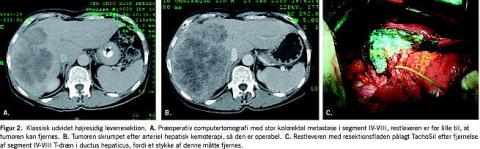

Operabiliteten er principielt uafhængig af størrelsen og antallet af tumorer samt deres lokalisation i leveren, mens prognosen dog er afhængig af disse forhold (Figur 1 ) [1]. I en normal lever tåles resektion af op til 75-80% af det totale levervolumen, under forudsætning af at leverresten sikres normal perfusion. Ved cirrose tåles langt mindre resektioner [2], og her kan lokalbehandling i form af radiofrekvensablation (RFA), alkoholinjektionsbehandling, kemoembolisering eller stereotaktisk strålebehandling være mulige alternativer. Ved særlig store resektioner kan præoperativ embolisering af v. portae overvejes mhp. at opnå vækst af den kontralaterale leverrest, idet dog en risiko for samtidig tumorvækst ikke kan udelukkes (Figur 2 ) [3].

I alle tilfælde anvendes der elkoagulation med spraystrøm eller argon-beaming suppleret med lokale hæmostatika på resektionsfladen i form af TachoSil, FloSeal eller Lyostypt (Figur 2B).